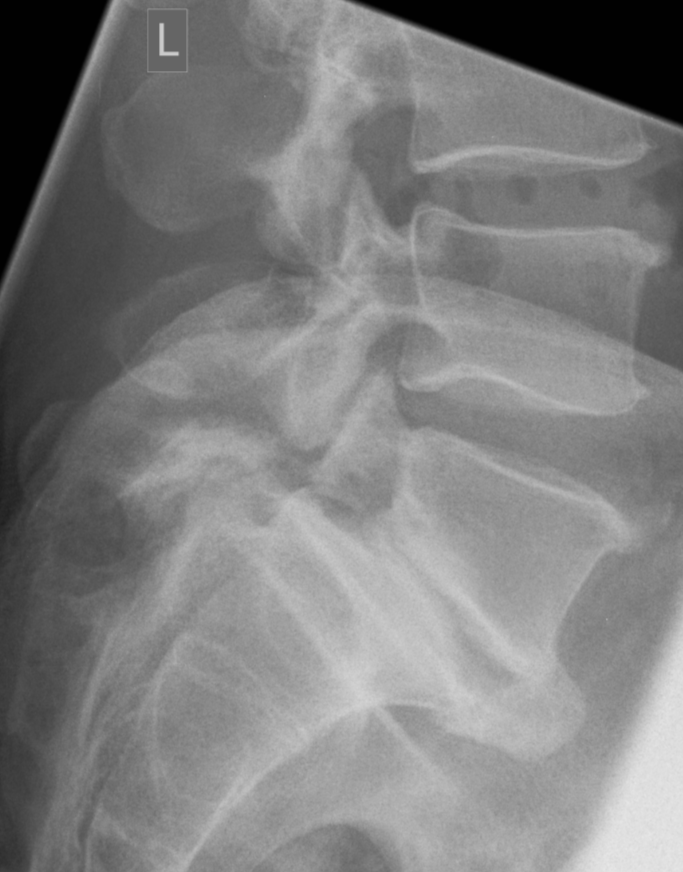

3. Spondylolisthesis due to pars defects